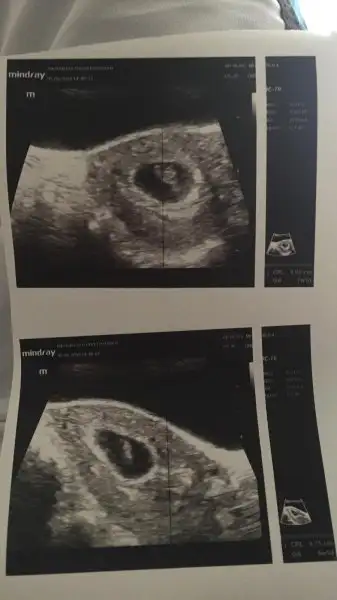

Ramzi teorisine göre ( bilimsel bir araştırma sonucuymuş ve %85 doğruluğu varmış). İlk 6-8 haftalık ultrason görüntüsüne göre bebeğin kesenin içersinde soldan ya da sağdan girişine göre cinsiyet tahmini yapılıyor. Bilimsel olunca tecrübeli annelerimiz yada anne adaylarımızdan yardım istiyoruz. Doğruluğu var mı öğrenmek adına :) Bizleri aydınlatırsanız çok seviniriz. bu teorieye göre;

Vajinal muayeneyle bakıldıysa eğer;

Sağdan girmiş gözüküyosa aslında solmuş ve ERKEK,

Soldan girmiş gözüküyosa aslında sağmış ve KIZ ,

Karından bakıldıysa eğer,

Soldan girmiş gözüküyosa gerçektede solmuş ve ERKEK,

Sağdan girmiş gözüküyosa gerçekte de sağmış ve KIZ,

Kız :)Eki Görüntüle 2149251 kızmı erkek mi sizce